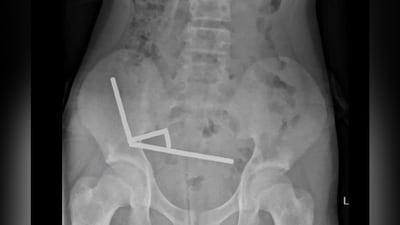

The magnets, bought online despite a decade-old ban, formed chains inside the boy’s intestines, forcing doctors to remove parts of his damaged organs. (IMAGE: NEW ZEALAND MEDICAL JOURNAL)

They discovered that the magnets had joined together to form four chains inside his intestines. According to the New Zealand Medical Journal, doctors said that boy had swallowed “approximately 80–100 5x2mm high-power neodymium magnets" a week prior to his hospitalization.